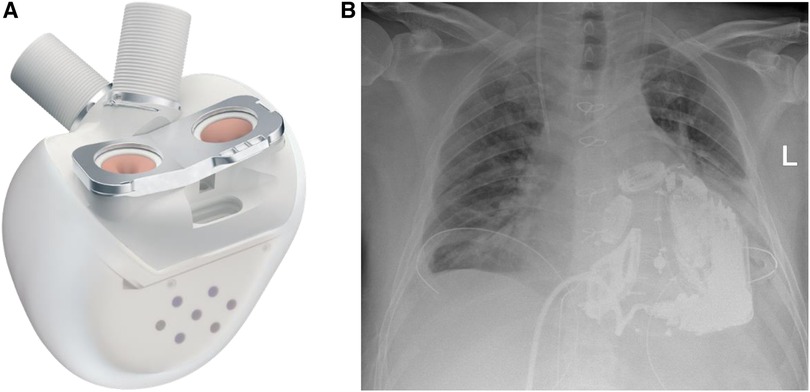

The surgical procedure started with a surgical preparation of the groin vessels followed by median sternotomy and aortic and bicaval cannulation. Cardiopulmonary Bypass (CPB) with central cannulation was initiated and the ECMO cannulas were removed surgically. At full CPB flow, the aorta was cross-clamped, as distally as possible. The native ventricles were excised one centimeter above the atrio-ventricular plane. To reduce the risk of air embolism, CO2 was flushed into the pericardial space. Two bioprosthetic atrial cuffs with central openings were sewn to the annuli with two layers of running sutures. A rectangular titanium interface was placed and secured to the cuffs. The Aeson device, mounted with four biological valves and two outflow conduits, was attached to the atrial interface (Figure 3). The Dacron outflow conduits were then connected to the pulmonary and the aorta with running sutures and re-enforcing patches. The driveline was tunneled through the right rectus muscle with skin exit at the lower right abdominal quadrant. The device was then connected to the portable controller. The TAH was first passively filled and de-aired with a vent placed in the ascending aorta. Pump beat rate and stroke volume were gradually increased while CPB support was weaned. Shortly after careful volume administration, the TAH was able to achieve stable cardiac output, and a substantial decrease in the catecholamines was achieved.

Figure 3. (A) The Aeson TAH device, courtesy of CARMAT (SA, Vélizy, France). (B) Chest x-ray of the patient after Aeson TAH implantation.